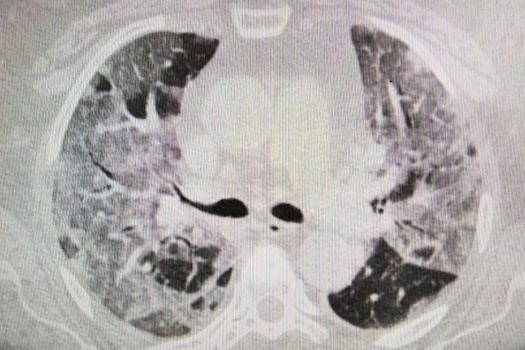

Сейчас в инфекционном госпитале больницы находятся больше двухсот человек. Кого-то выписывают, но на их место тут же везут новых. Врачи рассказывают, что большая часть из поступивших переносят COVID-19 легко — таких примерно 80%. Остальные 20% — очень тяжёлые. Это именно те, кто в зоне риска, в том числе пожилые и люди с хроническими заболеваниями. Спасти удается не всех.